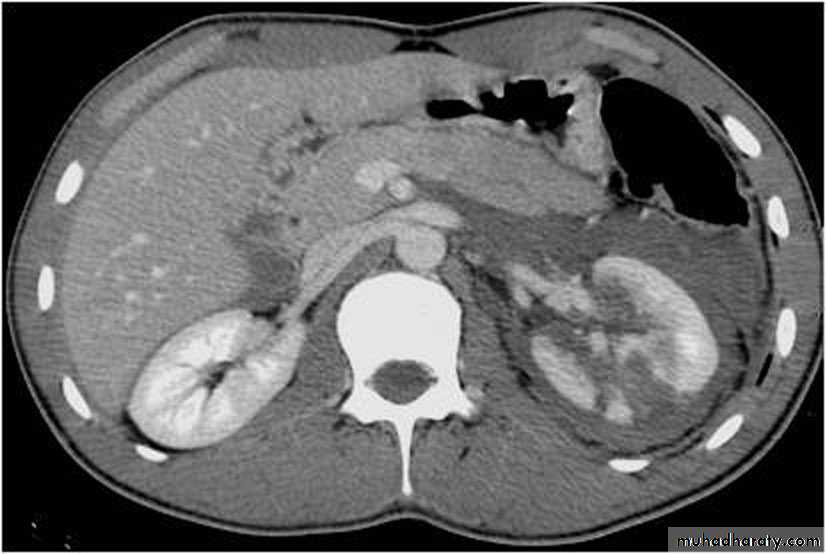

Renal trauma

The kidneys and the spleen are the most internal organs to be injured (¾ blunt and ¼ penetrating)CT is the best investigation

1. It demonstrate the presence or absence of perfusion to the injured kidney

2. It insure that the opposite kidney is normal

3. it show the extent of renal parenchyma damage

4. It demonstrate injuries to other organs